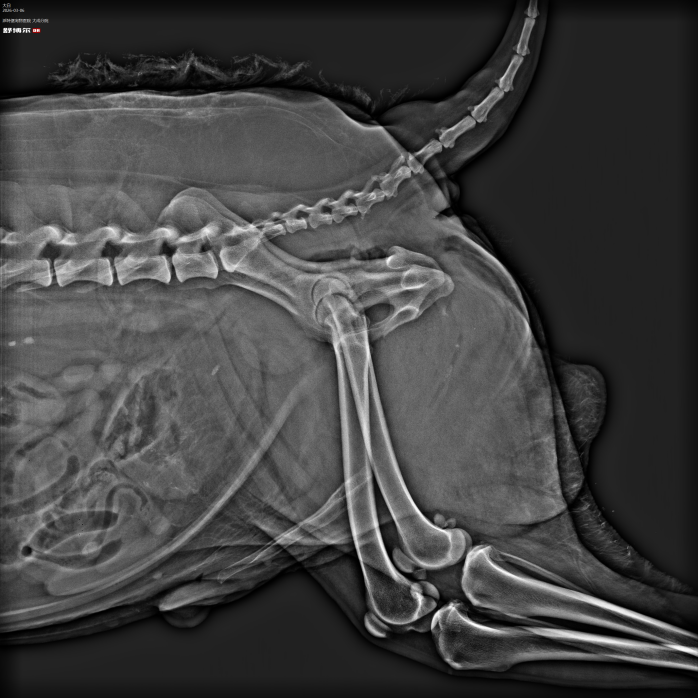

1.病例名称:铥激光+尿道内窥镜无创碎石术

2.患宠信息:10岁老龄犬

3.就诊原因:因尿道结石导致尿闭,无法正常排尿,精神沉郁,腹部胀满。

4.诊断难点:患宠年龄较大,麻醉风险高;结石位置深、分布广,同时累及尿道与膀胱,传统开刀手术创伤大、恢复慢。

5.治疗过程:采用铥激光碎石联合尿道内窥镜取石技术,在无需开刀、无需全身麻醉的情况下,精准定位结石,逐层粉碎并同步取出,全程无创完成尿道及膀胱内结石清除,最大限度降低手术风险。

6.康复情况:术后排尿通畅,精神状态良好,次日恢复正常饮食活动,无并发症,恢复周期显著缩短。